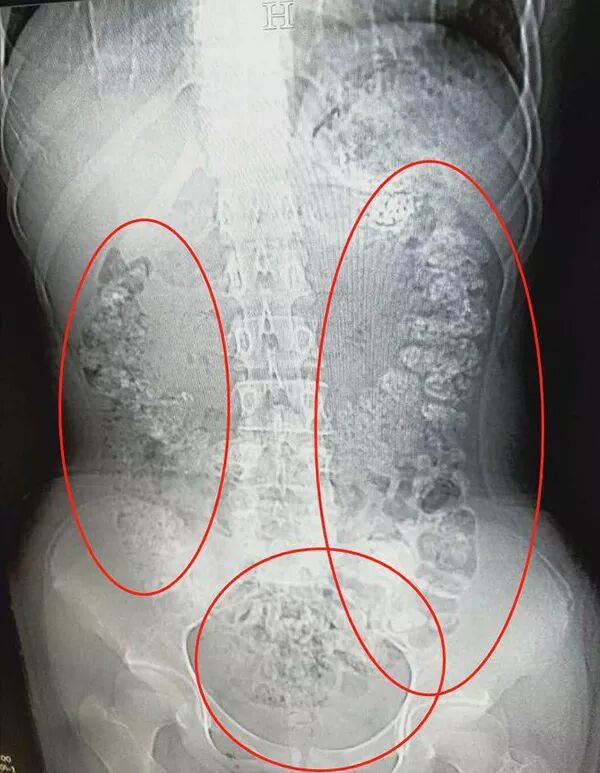

14岁女孩喝了珍珠奶茶后,五天没有排便,还肚子疼,CT检查发现胃肠道布满一颗颗圆圆的高密度阴影——没有消化的“珍珠”。

5月28日晚,女孩小沈(化名)在父母陪同下到浙江诸暨市人民医院急诊,说肚子疼,几天无法排便,也吃不下东西。接诊医生张楼炜见她肚子鼓鼓的,便安排了腹部CT,检查结果让他一惊:患者胃部、横结肠、升结肠、降结肠、乙状结肠,一直到肛门,全是颗粒状阴影,足有百余颗